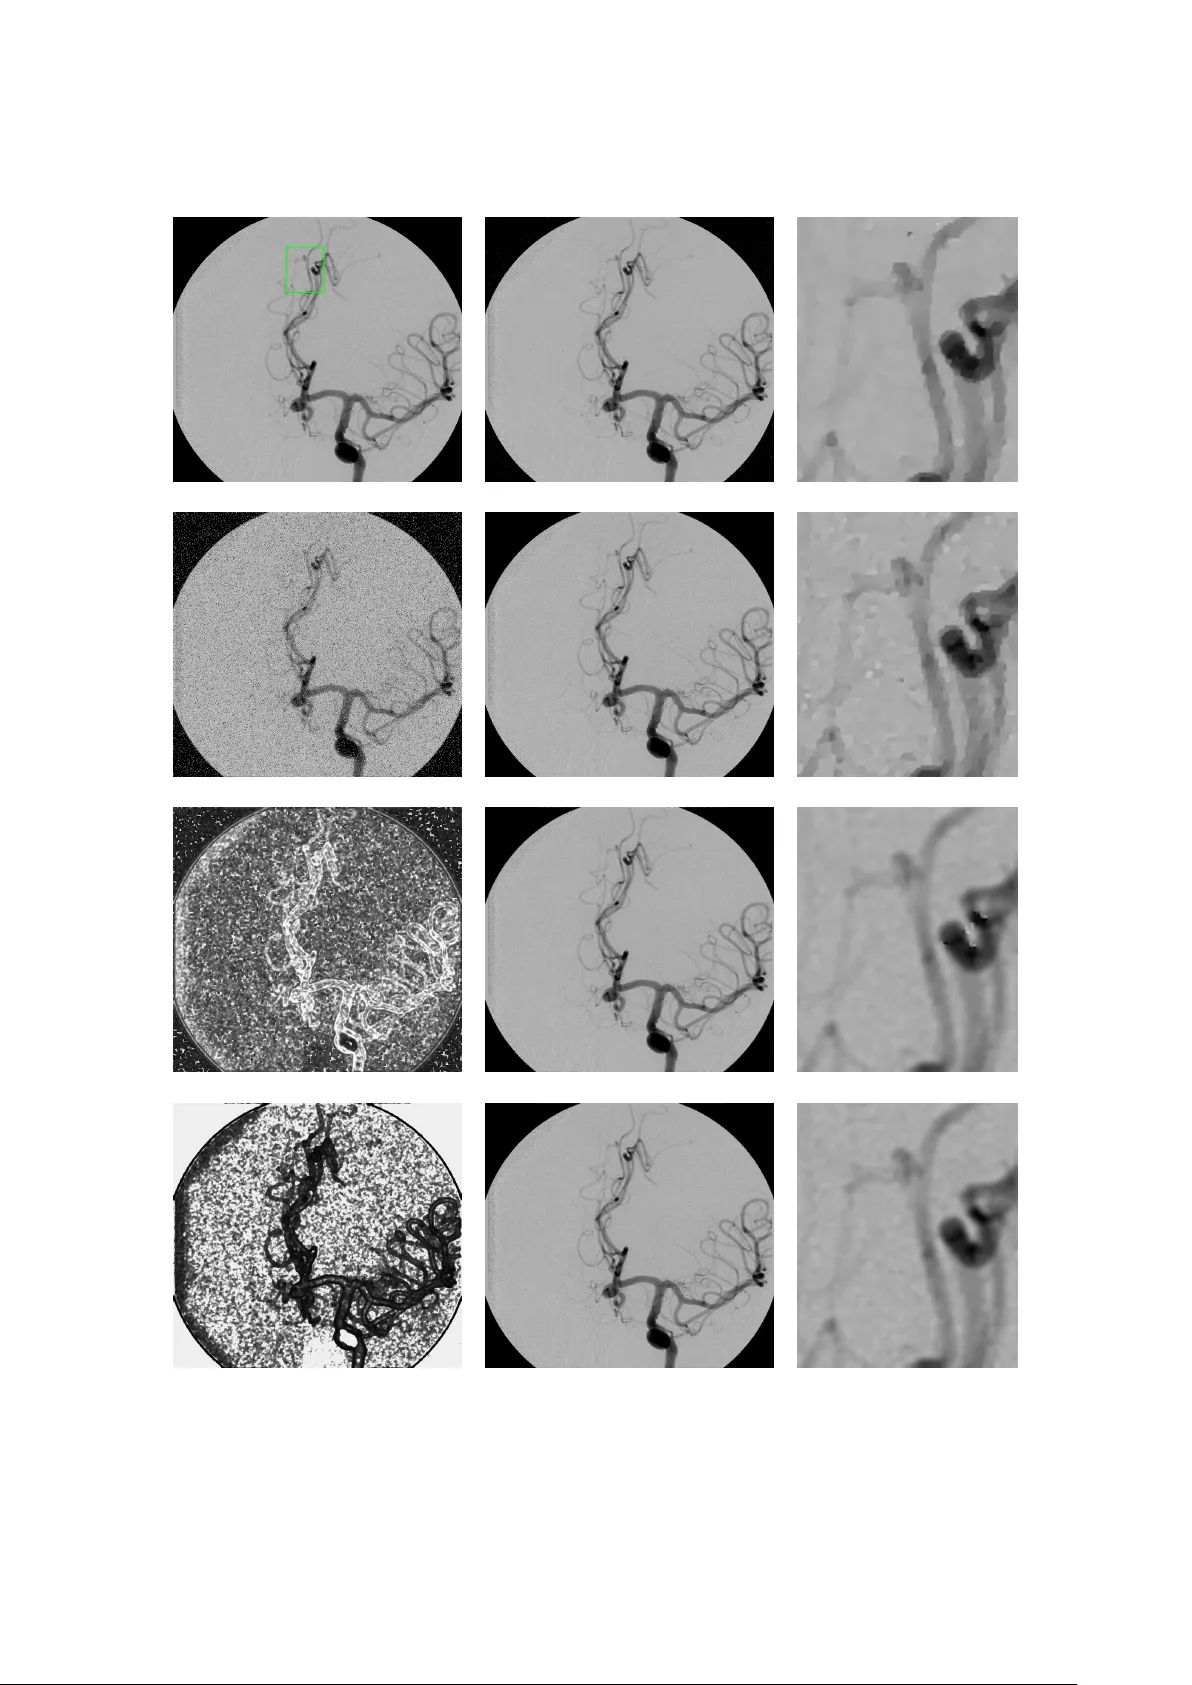

본 논문은 이미지 복원 문제에 대해, 각 픽셀 주변의 그래디언트 크기가 반-일반화 가우시안 분포를 따른다는 가정 하에 공간 가변 정규화 항을 제안한다. 두 개의 자유 파라미터 pᵢ와 αᵢ를 픽셀별로 자동 추정하고, L₂(가우시안 잡음)와 L₁(라플라스·소금·후추 잡음) 데이터 적합 항과 결합하여 ADMM 기반 반복 알고리즘으로 효율적으로 최적화한다. 실험 결과, 다양한 이미지와 잡음 유형에 대해 기존 TV·TVᵖ 모델보다 우수한 복원 품질을 보…

본 논문은 이미지 복원 문제를 변분 프레임워크 안에서 다루며, 기존의 Total Variation(TV) 정규화가 갖는 전역적인 형태 파라미터(p=1)와 스케일 파라미터(α 고정)의 한계를 극복하고자 한다. 저자들은 목표 이미지의 그래디언트 크기 ‖∇u‖₂가 위치에 따라 서로 다른 반‑일반화 가우시안(hGG) 분포를 따른다고 가정한다. hGG는 두 파라미터 p와 α로 정의되며, p는 형태(shape) 파라미터, α는 스케일 파라미터이다. 이 가정을 MAP 추정식에 적용하면, 사전 확률 Pr(u)∝exp(−∑ᵢ αᵢ‖∇uᵢ‖₂^{pᵢ})가 된다. 따라서 정규화 항은 TVₛᵥ^{p,α}(u)=∑ᵢ αᵢ‖∇uᵢ‖₂^{pᵢ} 와 같이 각 픽셀마다 다른 pᵢ와 αᵢ를 부여하는 공간‑가변 형태가 된다. 이는 기존 TV(α·‖∇u‖₁)와 TVᵖ(α·‖∇u‖_{p}^{p})의 일반화이며, 특히 텍스처가 풍부한 영역과 평탄한 영역을 동시에 효과적으로 처리할 수 있다. 파라미터 추정은 두 단계로 수행된다. 첫 번째 단계에서는 형태 파라미터 pᵢ를 추정한다. 각 픽셀 i를 중심으로 크기 s(3,5,… )의 정사각형 이웃 Nₛᵢ를 정의하고, 그 안의 그래디언트 크기 mⱼ=‖∇uⱼ‖₂를 수집한다. 이후